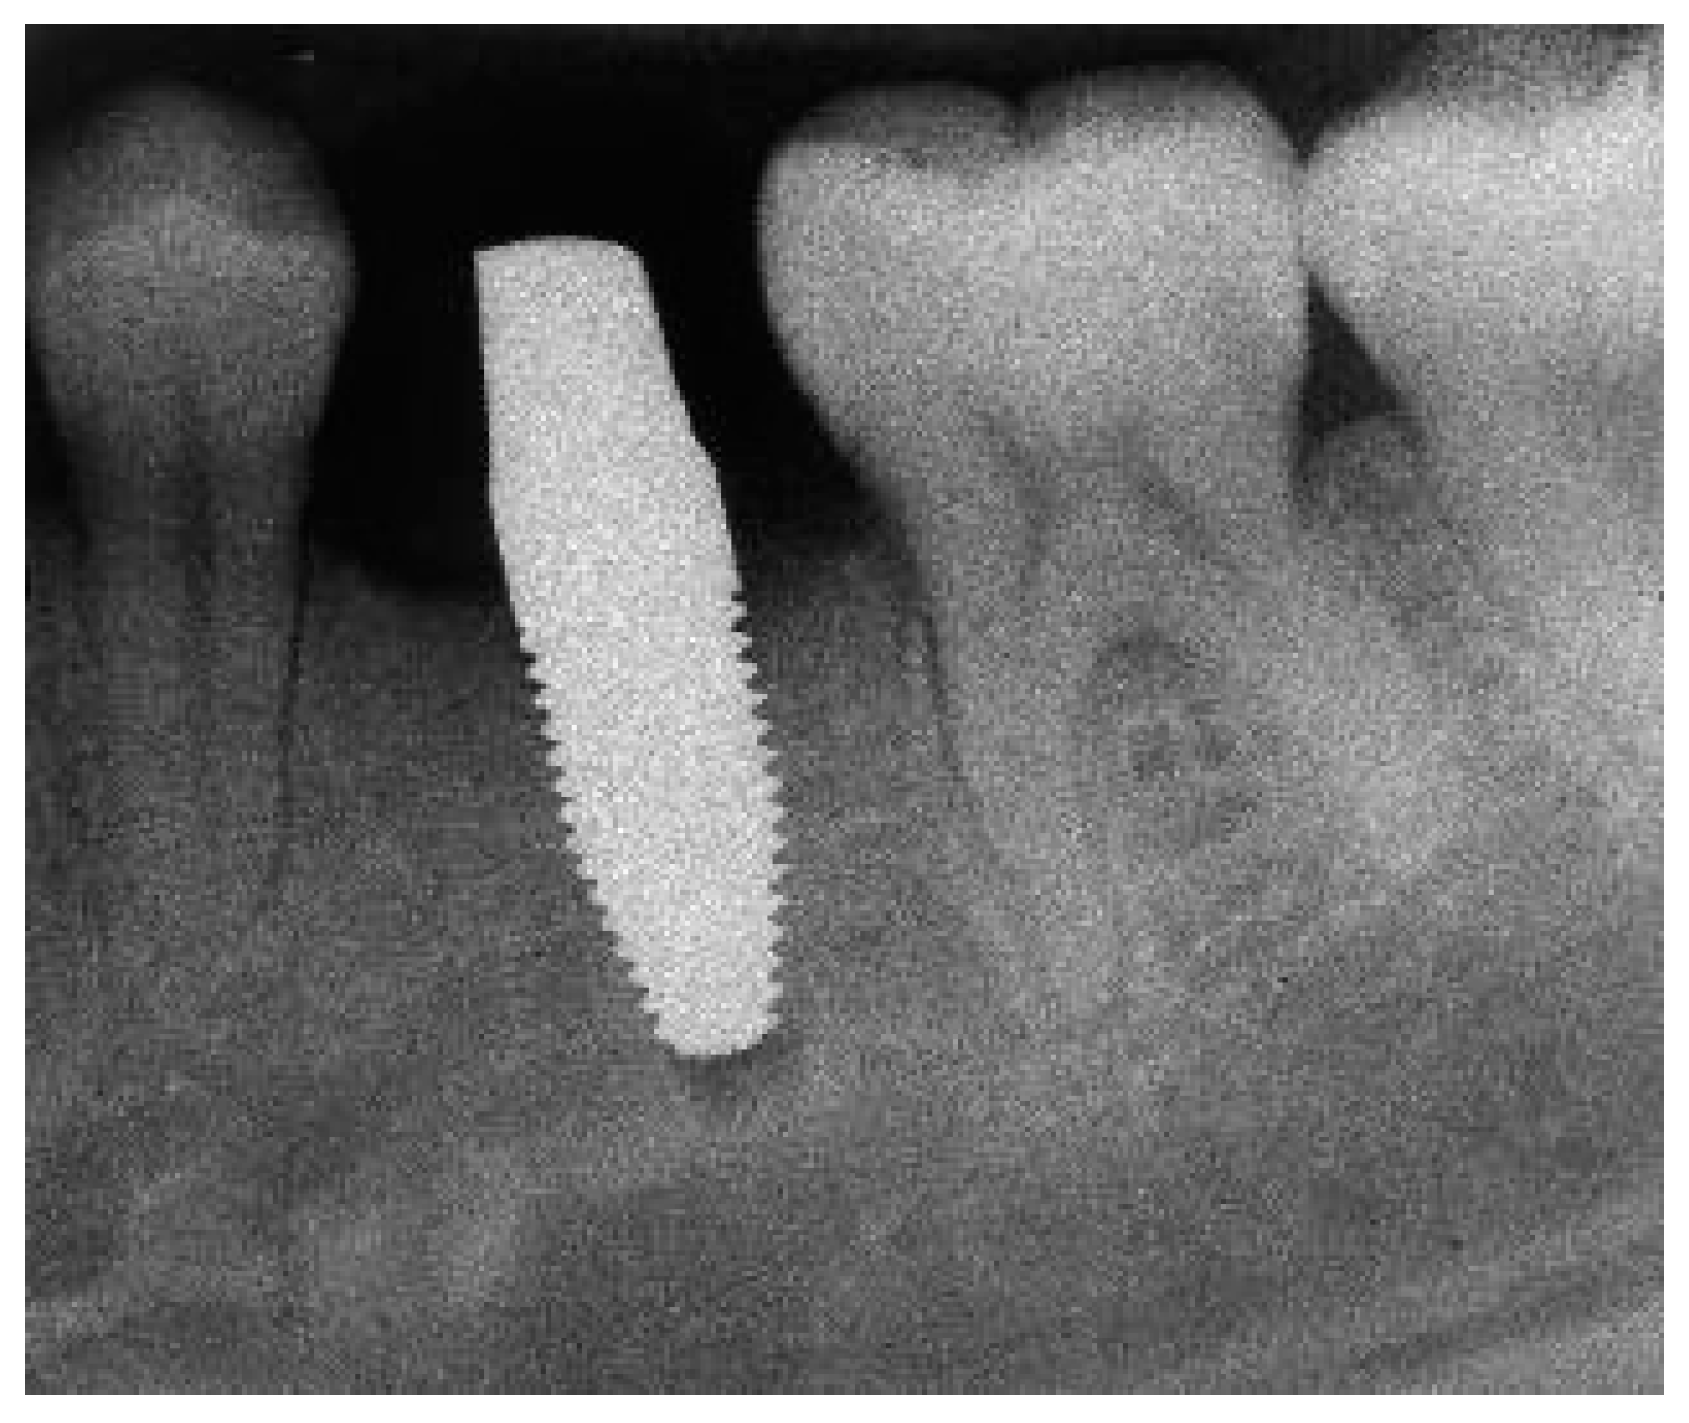

Radiograph of the perimplant bone situation before crown cementation.

Figure A3.

Radiograph of the perimplant bone situation at the 1-year follow-up.

Figure A6.

Radiograph of the perimplant bone situation at the 3-year follow-up.

Figure A9.

Radiograph of the perimplant bone situation at the 5-year follow-up.

Figure A12.